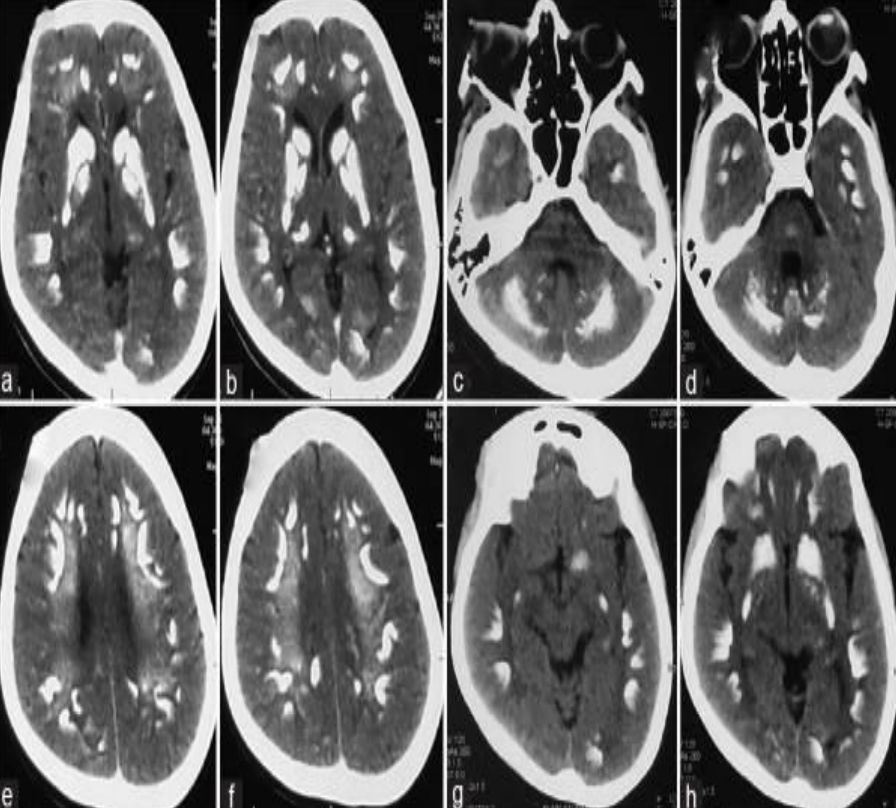

患儿女性,8岁,反复呕吐半年,3年前有癫痫发作,未诊治。

答案:Sturge-Weber综合征(SWS)。

补充资料:患儿右侧眼眶、颜面部见大片红色斑块,无溃疡。患儿癫痫、呕吐,颅内皮层脑回状钙化,大血管未见畸形,考虑SWS。在没有CT的情况下,本病例诊断存在困难。Sturge-Weber综合征又称脑颜面血管瘤病、脑颜面三叉神经血管瘤病、软脑膜血管瘤病等,是先天性颜面与脑混合性血管畸形,病变的主要特点为面部三叉神经分布区皮肤血管瘤和同侧软脑膜血管瘤。钙化多发生于软脑膜血管瘤下的脑皮质,并可累及整个皮层,但常见于第2~3层。钙化早期位于血管周围,以后位于血管瘤和周围组织之间。钙化有脑回状、斑块状、点状、条状等多种形态,以脑回状为特征。